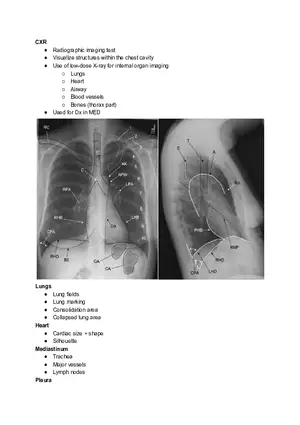

Chest X-ray (CXR)